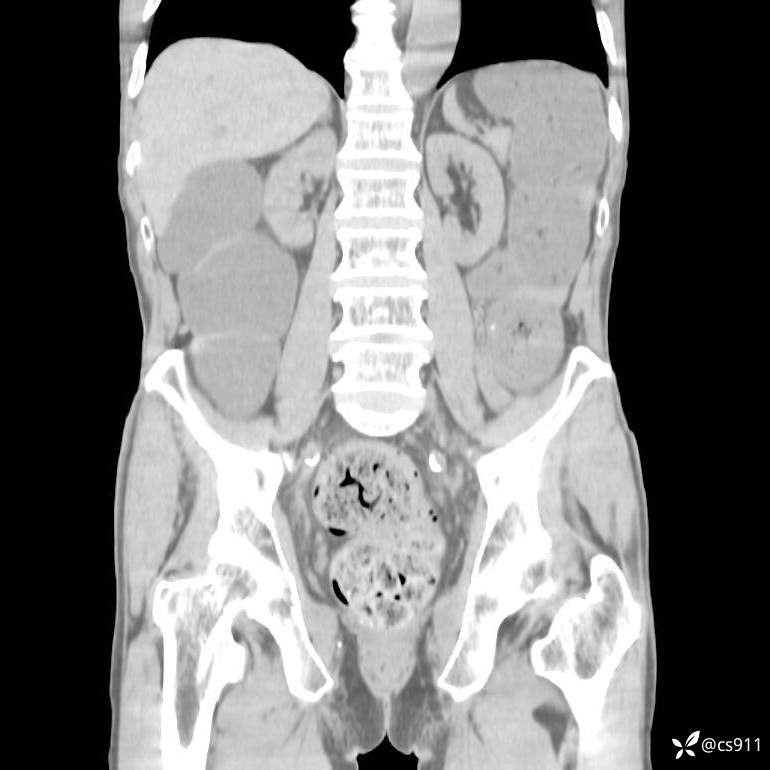

急腹症之急诊CT,原因?答案公布

男,77岁,腹痛、腹胀伴恶心呕吐1天。呕吐胃内容物,非喷射性呕吐,有咖啡色样胃内容物,诉有胃穿孔病史。查体:全腹平,下腹部压痛,全腹无反跳痛,叩诊呈浊音,移动性浊音阴性,肠鸣音减弱,1-2次/分。肛检:直肠未扪及明显肿物,可触及大量粪块。

T 36.6℃ P 80次/分 R 26次/分 BP 100/60mmHg

白细胞(WBC) H 14.55 10e9/L 4-10

中性粒细胞百分率(NEUT%) H 85.7 % 40-75

血淀粉酶(AMY) HH 1859 U/L 35-135

癌胚抗原(CEA) H 27.44 ng/ml 0-5

呕吐物 潜血试验 * 阳性 阴性

患者轮椅入室检查神志清楚, 能配合摆位和呼吸